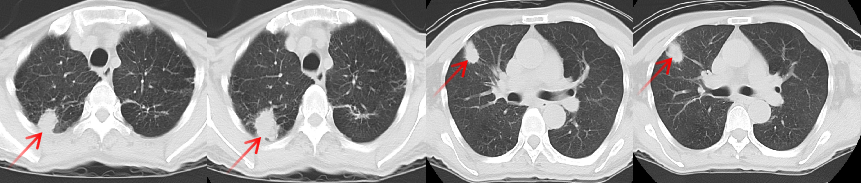

張老太,70歲, 2024年8月因頭暈頭痛,頻繁嘔吐等癥狀入院。頭部磁共振檢查顯示,顱內(nèi)多發(fā)腦轉(zhuǎn)移瘤病灶(見圖)。同時(shí),患者胸部CT檢查可見肺內(nèi)多發(fā)較大腫瘤病灶(見圖)?;颊哂?024年8月20日行CT引導(dǎo)肺腫物穿刺活檢。病理診斷為肺腺癌。綜合診斷為肺腺癌IVB期,腦、肺內(nèi)、右腎上腺多發(fā)轉(zhuǎn)移?;颊哌M(jìn)一步行腫瘤組織基因檢測(cè)和免疫檢查點(diǎn)分子——細(xì)胞程序性死亡配體1(PDL1)檢測(cè)。

圖注:胸部CT檢查,肺內(nèi)多發(fā)較大腫瘤病灶。

患者于2024年08月20開始接受頭部放療。采用最新一代智慧化精準(zhǔn)放療系統(tǒng)——Halcyon“速銳刀”,成功控制患者全部顱內(nèi)病灶,過程順利,沒有明顯副反應(yīng)發(fā)生。患者基因檢測(cè)結(jié)果為陰性,沒有找到具有靶向治療藥物的突變基因。此外,患者年齡較大,體質(zhì)較弱,全身多發(fā)轉(zhuǎn)移病灶,為治療帶來了巨大的挑戰(zhàn)。然而,患者PDL1檢測(cè)顯示,PDL1高表達(dá)(PD-L1 TPS=98%),提示免疫治療有效率較高。潘振宇教授團(tuán)隊(duì)為患者制定了個(gè)體化精準(zhǔn)腫瘤治療方案,僅僅每3周應(yīng)用1次免疫治療藥物。經(jīng)過3次治療后復(fù)查,患者肺內(nèi)病灶顯著縮退,顱內(nèi)病灶縮退。治療過程中,僅出現(xiàn)一過性皮疹。目前患者恢復(fù)良好,生活完全自理。

圖注:治療后復(fù)查胸部CT顯示,肺內(nèi)病灶明顯縮小。